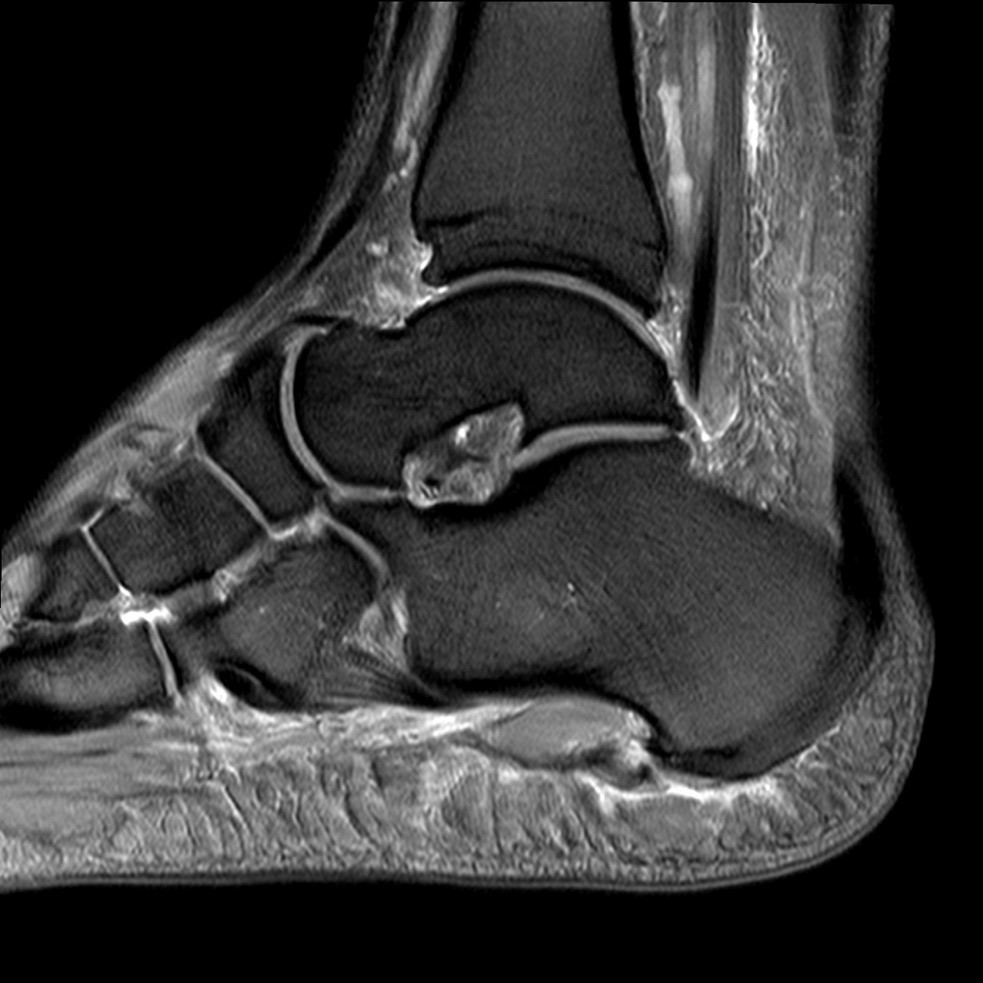

Abb. 2: Teilruptur Plantaraponeurose in der MRT Diagnostik

Eine Teilruptur der Plantaraponeurose kann ursprungsnah oder auch einige cm distal des Ursprungs als Folge einer direkten Gewalteinwirkung auftreten.

Zum Lesen der Bildbeschreibung und zur Vollansicht bitte das Bild anklicken. Bild: Manfred Thomas

In seltenen Fällen findet sich eine komplette Ruptur der Plantaraponeurose als Ursache der Beschwerden (siehe Abb. 3).